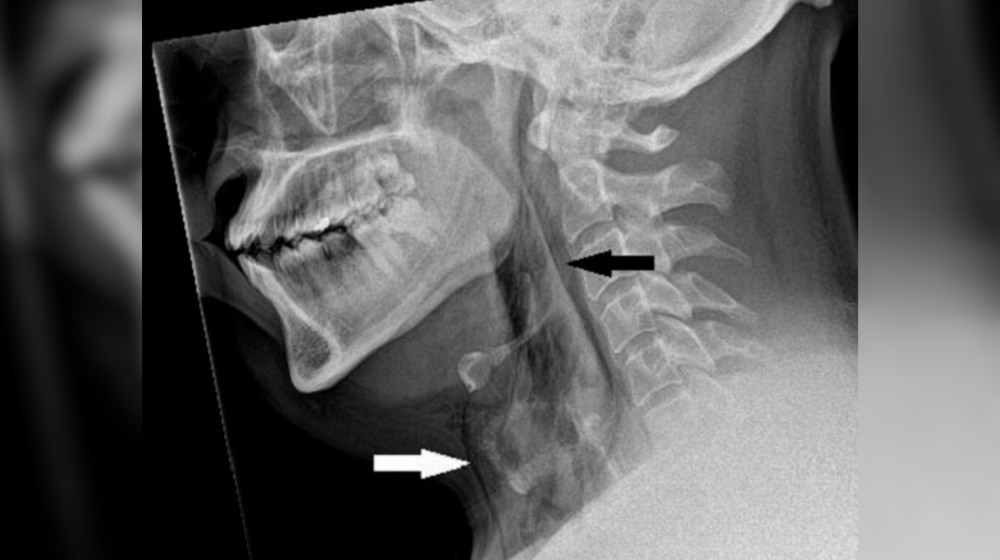

Мужчина сдержал чихание и продырявил трахею

Этот медицинский случай из Великобритании заставил врачей пересмотреть привычные рекомендации. Пациент в возрасте 30+ лет обратился в отделение неотложной помощи с острой болью и отеком шеи. Си...